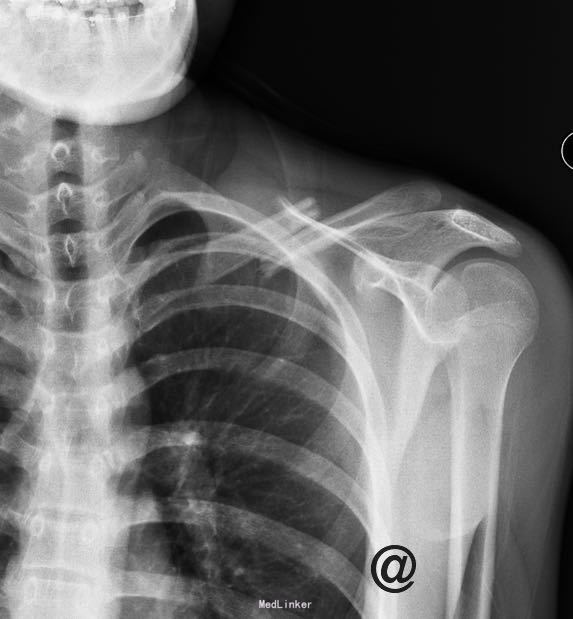

主诉:摔伤致左肩部疼痛活动受限6小时 现病史:患者自诉于2014年6月26日上午9点多骑自行车时与对面行驶的自行车相撞,当时摔倒致左锁骨区疼痛,肿胀,左肩活动受限,当时无意识不清,急诊就诊于中国医科大学附属盛京医院,行X线片检查示:左锁骨骨折,急诊以“左锁骨骨折”为诊断收住入院。伤来患者无头痛及发热,无咳嗽咳痰,无腹痛及恶心呕吐,饮食睡眠可,大小便正常。

专科检查:左上肢吊臂带固定中,左侧锁骨中段可见畸形,可触及骨擦感,压痛(+),肿胀,左肩活动受限,左上肢无明显麻木,桡尺动脉清楚,各手指感觉活动可。

诊断:左锁骨骨折 患者入院后完善生化检查,示血气分析结果可排除血气胸等,无明显手术禁忌症行左锁骨骨折切开复位钢板内固定术。术后给予止疼,消肿,接骨等对症治疗。